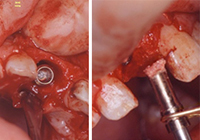

通常のインプラント手術は、抜歯後に歯肉が治癒してから顎にドリルで穴をあけてインプラントを埋入します。しかし、事故など予期せぬトラブルに見舞われて歯を失ったり、欠けたりした際には、必要に応じて即インプラントを埋入する手術を行うことも可能です。

唇側の骨を傷つけないよう注意しながら、ペリオトームという専用器具を使って抜歯を行います。

唇側層板骨量(唇側の薄い骨)を確認するため、慎重に歯周組織を診断・剥離します。インプラント(人工歯根)の最適な大きさ・形状を再度確認し、挿入位置を確認しながら埋入していきます。